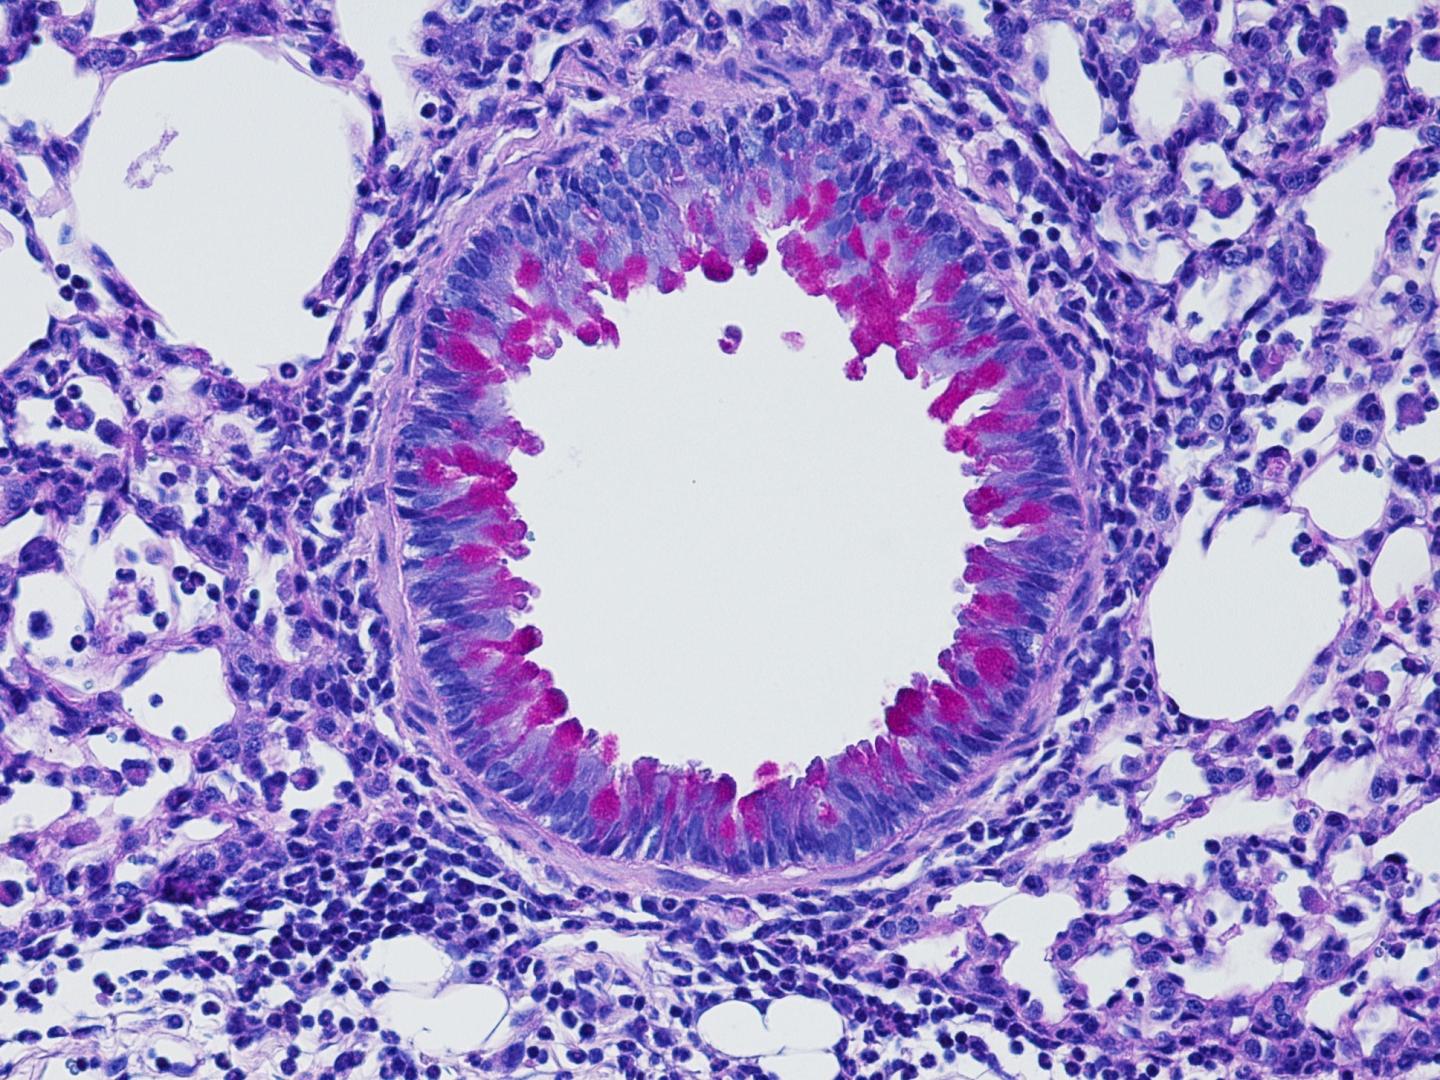

For their study, Dr. Artis and his colleagues examined communication between the nervous system and immune system during the kind of inflammatory response that is triggered by allergens or infections with parasites called helminths. Exposure to these agents causes a class of immune cells called group 2 innate lymphoid cells (ILC2) to release inflammatory molecules called cytokines that can promote increased mucus production and muscle contractions--all of which help to expel the parasite or allergen from the body. Too much or prolonged inflammation can be harmful, so Dr. Artis and his team wanted to understand how the body dampens this response.